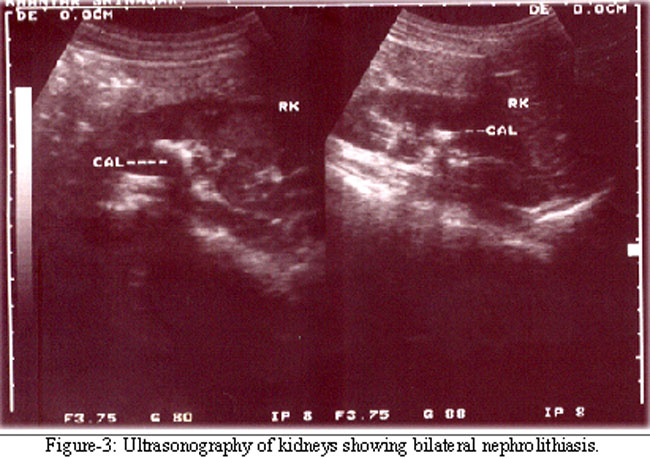

At the age of 11 years dose of calcitriol was increased to 0.5 g/day and calcium to 750mg/day with monitoring of serum calcium every 3-6 months which were within normal limits. Meanwhile the girl attained menarche at the age of 13 years. At the age of 14 years she developed left flank pain and haematuria. Ultrasonography revealed multiple stones biggest being around 0.87×0.79mm in right middle and lower calyces without any hydronephrosis (Figure-2).

Urine analysis revealed hypercalciuria on multiple occasions (urinary calcium of 365-633mgs/day (normal up to 200mgs/day). Serum calcium was 10.51 mgs/dl (Normal value 9.5-11.5mgs/dl). Calcitriol and oral calcium were stopped, which lead correction of hypercalciuria. Repeat ultrasonography did not reveal any further increase in size of the previous stones or formation of new stone. Patient is off calcitriol and calcium for one year now and is under follow up with monitoring of serum calcium, phosphorus and alkaline phosphatase and urinary calcium and phosphorus. During follow up her serum calcium remained around 8.24 to 8.9mgs/dl and 24 hour urinary calcium excretion was around 4.92-8 mgs/day and no new radiological changes of rickets/osteomalacia have appeared.